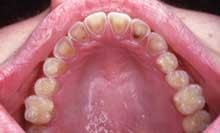

Intraoral examination revealed yellowish depressions on the lingual aspects of the maxillary teeth (see photo). The depressions appeared shallow, broad, smooth, and scooped out.

Another pattern of erosion that may occur presents as a smooth loss of enamel with exposure of dentin on the lingual surfaces of the maxillary teeth. If the lingual surface of the tooth is involved, a concave area of dentin surrounded by a thin, white line of enamel along the periphery of is seen. Chronic vomiting is associated with these characteristic changes of the lingual surfaces of the maxillary teeth. If the posterior teeth are involved, an extensive loss of enamel results on the occlusal surfaces. In posterior teeth with amalgam restorations, the edges of the restorations may extend above the level of the remaining tooth structure. Occasionally, entire cusps may be lost to erosion.